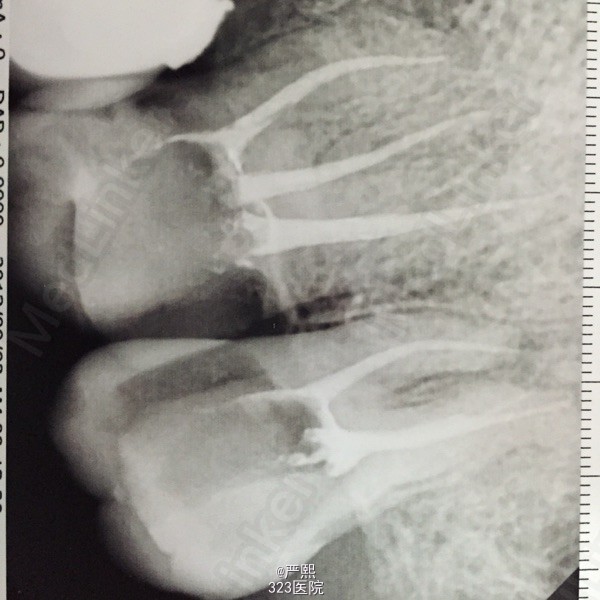

检查:26,27吻合邻面深龋坏,冷测极敏感,探痛明显,叩(+),松(-)。 辅助检查:RVG示26,27吻合邻面深龋坏,龋深及髓。26,27髓腔内可见大块髓石。

诊断:26,27牙髓炎 26,27髓石。 处理:26,27局麻下开髓,低速手机去除髓石,建立根管直线通路。Protaper扩至F1,测长:26,P:19mm,MB:18mm,DB:18.5mm。 27,P:18mm,MB:17mm,DB:17.5mm。双氧水生理盐水交替冲洗,试胶,干燥根管,封木棉。一周后复诊根管充填。

患牙根充后无不适,观察一周后,纤维桩加固,树脂修复,牙体预备,全冠修复。 讨论:去除髓石为本病例之难点,应使用慢速手机缓慢去除,其过程中应注意保护髓底,防止底穿和旁穿,必要时拍摄X线片确定是否去除完全。